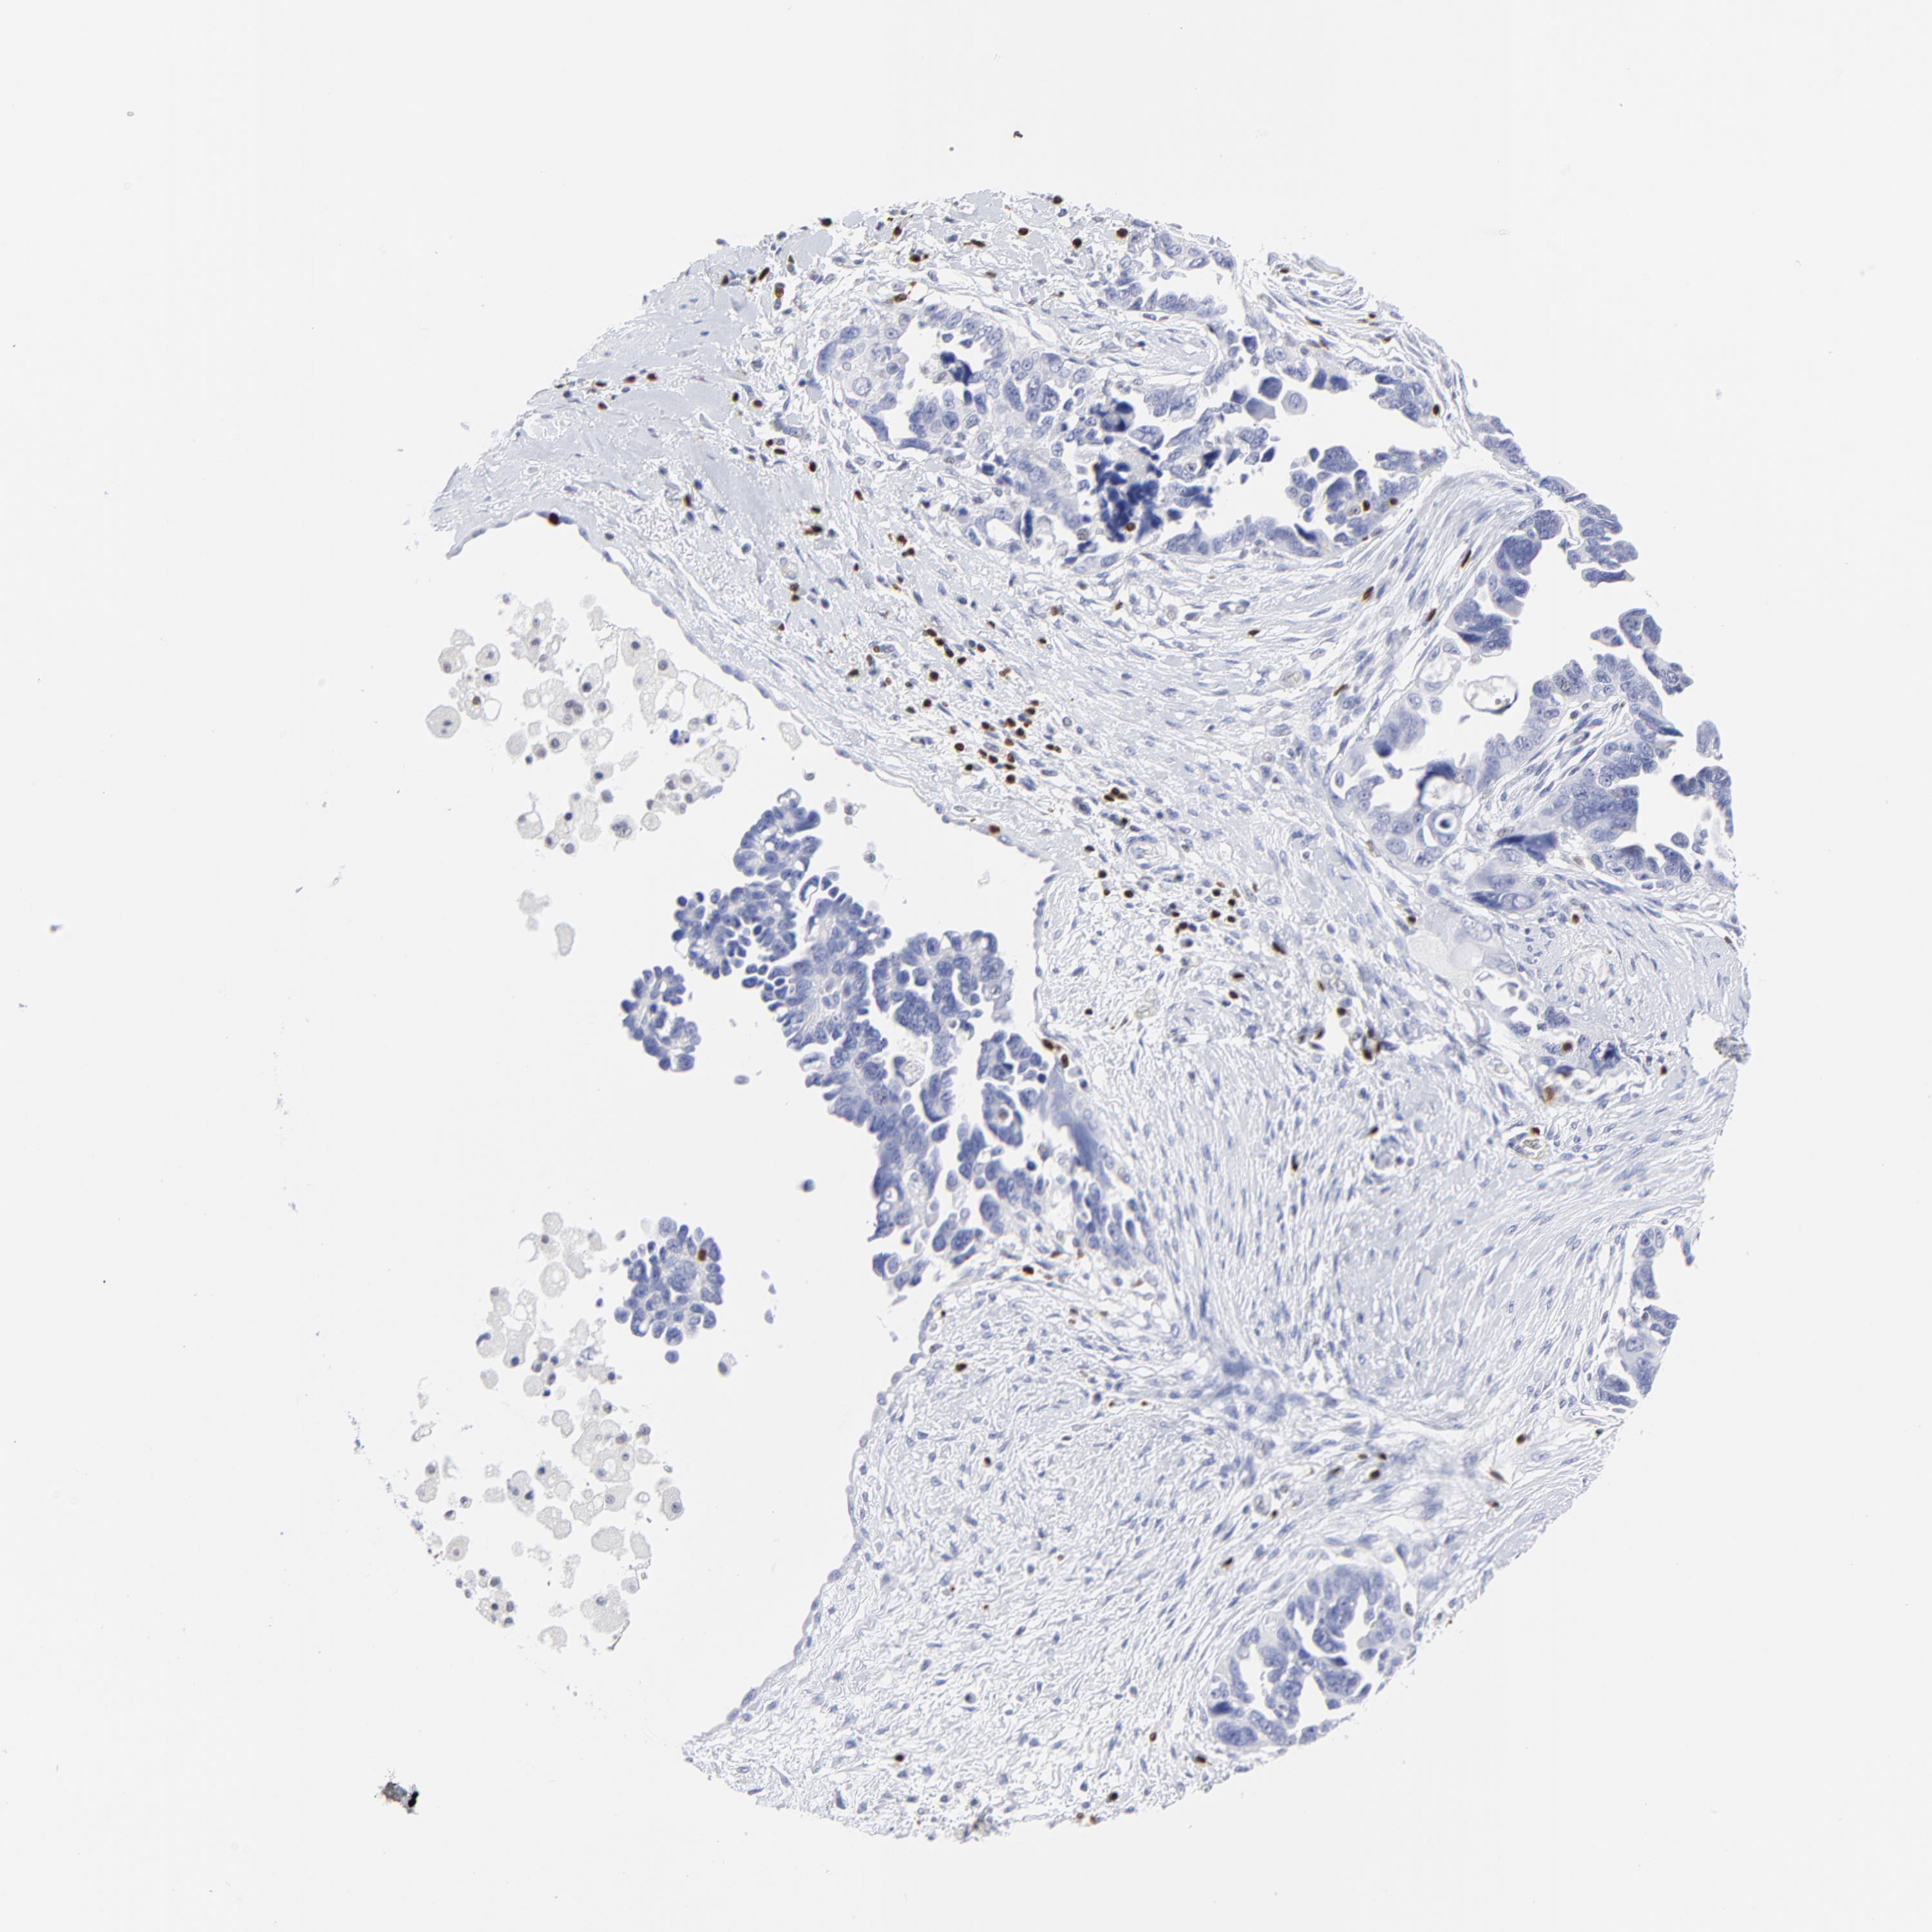

OVARIAN CANCER - Protein expressioni

A mouse-over function shows sample information and annotation data. Click on an image to view it in a full screen mode. Samples can be filtered based on level of antibody staining by selecting one or several of the following categories: high, medium, low and not detected. The assay and annotation is described here.

Note that samples used for immunohistochemistry by the Human Protein Atlas do not correspond to samples in the TCGA dataset.

Antibody stainingi

Antibody staining in the annotated cell types in the current human tissue is reported as not detected, low, medium, or high, based on conventional immunohistochemistry profiling in selected tissues. This score is based on the combination of the staining intensity and fraction of stained cells.

Each image is clickable and will lead to virtual microscopy that enables deeper exploration of all samples and also displays staining intensity scores, fraction scores and subcellular localization as well as patient and tissue information for each sample.

Antibody HPA003134

Antibody CAB002625

Cystadenocarcinoma, serous, NOS